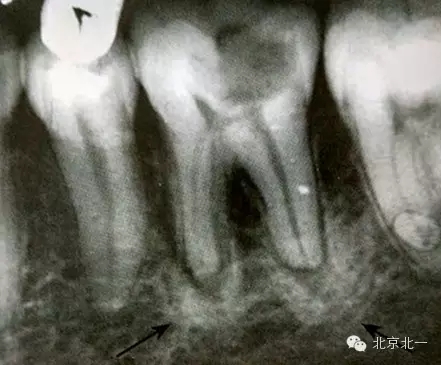

1)致密性骨炎

是指根尖周組織受到輕微緩慢持續(xù)性的低毒性因素刺激,而表現(xiàn)出以骨質(zhì)增生為主的防御性反應。一般無自覺癥狀,多見于青年人,下頜第一磨牙多見,常有較大齲壞。

【CBCT表現(xiàn)】:發(fā)生致命性骨炎的環(huán)亞暢游牙體病變,其CBCT表現(xiàn)為圍繞根尖的骨質(zhì)密度增高區(qū),骨小梁增多增粗,骨髓腔變窄甚至消失,與正常骨組織分界不明顯。根尖部牙周膜間隙可增寬,根尖無增粗膨大。

根尖片顯示D6深齲,根尖低密度區(qū)周圍骨小梁增粗、增多,骨質(zhì)密度增高,骨髓腔變小(黑色箭頭)。